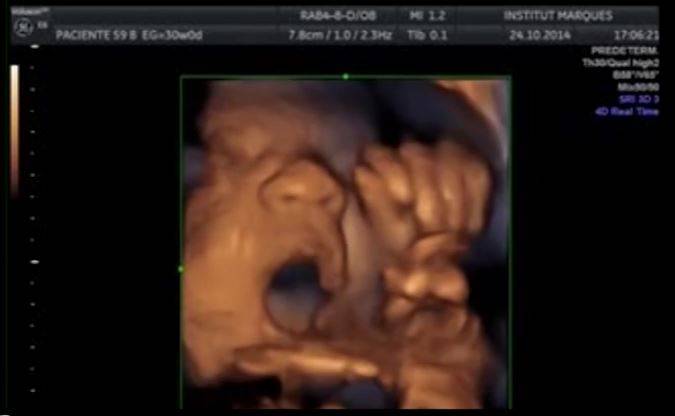

Bebè ascolta la musica nel pancione (Screenshot video Institut Marquès)

Facendo ascoltare Bach ai bebè nel pancione, tramite il dispositivo intravaginale, i ricercatori hanno scoperto con l’ecografia in 3D che i bambini si muovono, spostano la testa, agitano le braccia e tirano fuori la lingua. Insomma, la musica sembra piacere ai nascituri, secondo gli studiosi. L’87% di loro ha reagito con movimenti della testa, degli arti, della bocca e della lingua, movimenti che si sono fermati quando i bambini non hanno sentito più la musica.Il 50% dei bambini, invece, ha aperto molto la bocca tirando fuori tutta la lingua.

Ma la musica sarà piaciuta veramente a questi bambini, con tutte queste linguacce? Ricordiamo che si muovono molto nella pancia anche i bebè di madri fumatrici, e questo non  è un bene.